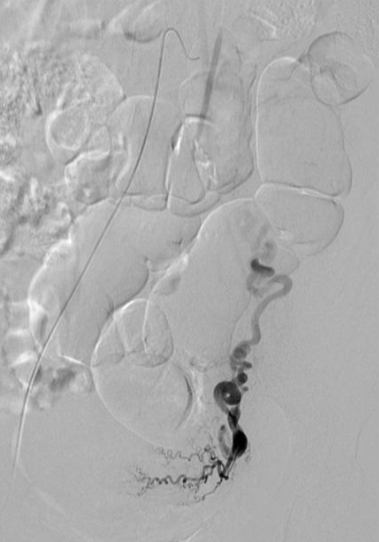

所有年龄超过 40 岁的患者, 卵巢受损 14%-43% 研究中闭经发生率(15%)与单纯UAE报告相似,可能与患者年龄(≥45岁)及卵巢储备自然下降有关。 ![]() 50岁,长期因子宫肌瘤导致月经出血过多,痛经和贫血。 子宫肌瘤栓塞术前,显示双侧子宫动脉发育不全,子宫肌瘤双侧卵巢动脉。 经皮股动脉穿刺双侧卵巢动脉栓塞,先500μm-700μm emboSphere 微球 术后4周,和6月的中短期随访,月经正常,子宫容积减少,贫血纠正,无卵巢功能衰竭。但看起来非灌注容积较少。 术后9月,由于子宫肌瘤持续存在,患者自己希望绝经,行全子宫和双侧卵巢切除术 术后病理,子宫内可见栓塞微粒伴有坏死,卵巢内也见栓塞微粒,但卵巢功能未受损。